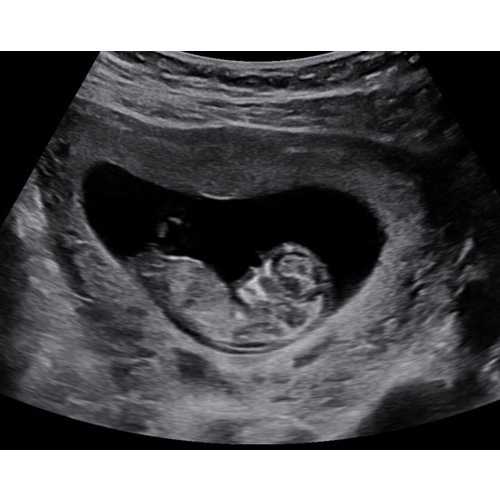

Vanmiddag de termijnen echo gehad, 19 oktober was ik 6 dagen terug gezet, vanmiddag bij de echo weer 6 dagen voorruit, de kleine deed het super, groeit goed en was een spring in het veld in de buik, heb een prachtig filmpje maar kan die niet plaatsen! Echt even een bevestiging van zwanger zijn! Ik heb 0.0 kwaaltjes dus maakte me toch wat zorgen dat het niet goed ging! Vandaag 11+4 wkn met de uitgerekende datum op 3 Juni 鉂も潳

Het is zo leuk!!! Geniet er lekker van! Zo鈥檔 bijzonder moment!! 馃槏 Het is nu echt een kindje met een neusje enzo wauw!

Ahh, mooie echo!!! Ik had ook vandaag nu 11+1馃挄